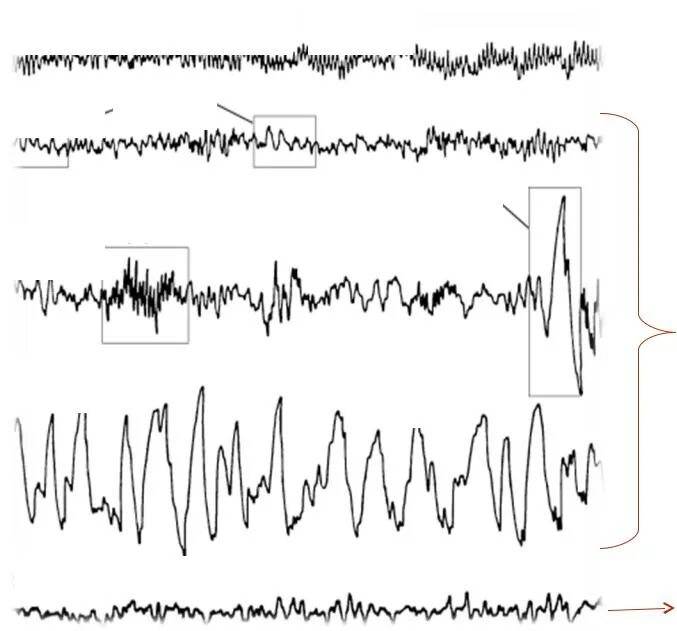

Ээг мониторинг головного мозга